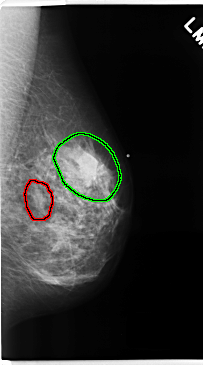

FILE: C_0229_1.LEFT_MLO.OVERLAY

TOTAL_ABNORMALITIES 2

ABNORMALITY 1

LESION_TYPE MASS SHAPE OVAL MARGINS CIRCUMSCRIBED

ASSESSMENT 3

SUBTLETY 5

PATHOLOGY BENIGN

TOTAL_OUTLINES 1

BOUNDARY

ABNORMALITY 2

LESION_TYPE MASS SHAPE IRREGULAR MARGINS SPICULATED

ASSESSMENT 5

PATHOLOGY MALIGNANT